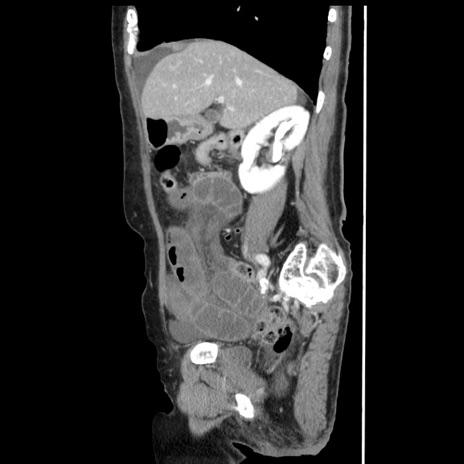

症例1(矢状断像)

【症例】80歳代女性

【主訴】腹痛

【現病歴】8時間前から腹痛あり来院。

【既往歴】糖尿病、脂質異常症、子宮体癌にて子宮全摘術

【身体所見】意識清明・会話良好だが腹痛で苦悶様、全腹部にわたって反跳痛と圧痛あり

【データ】WBC 13600、CRP 0.14、LDH 224、CK 90